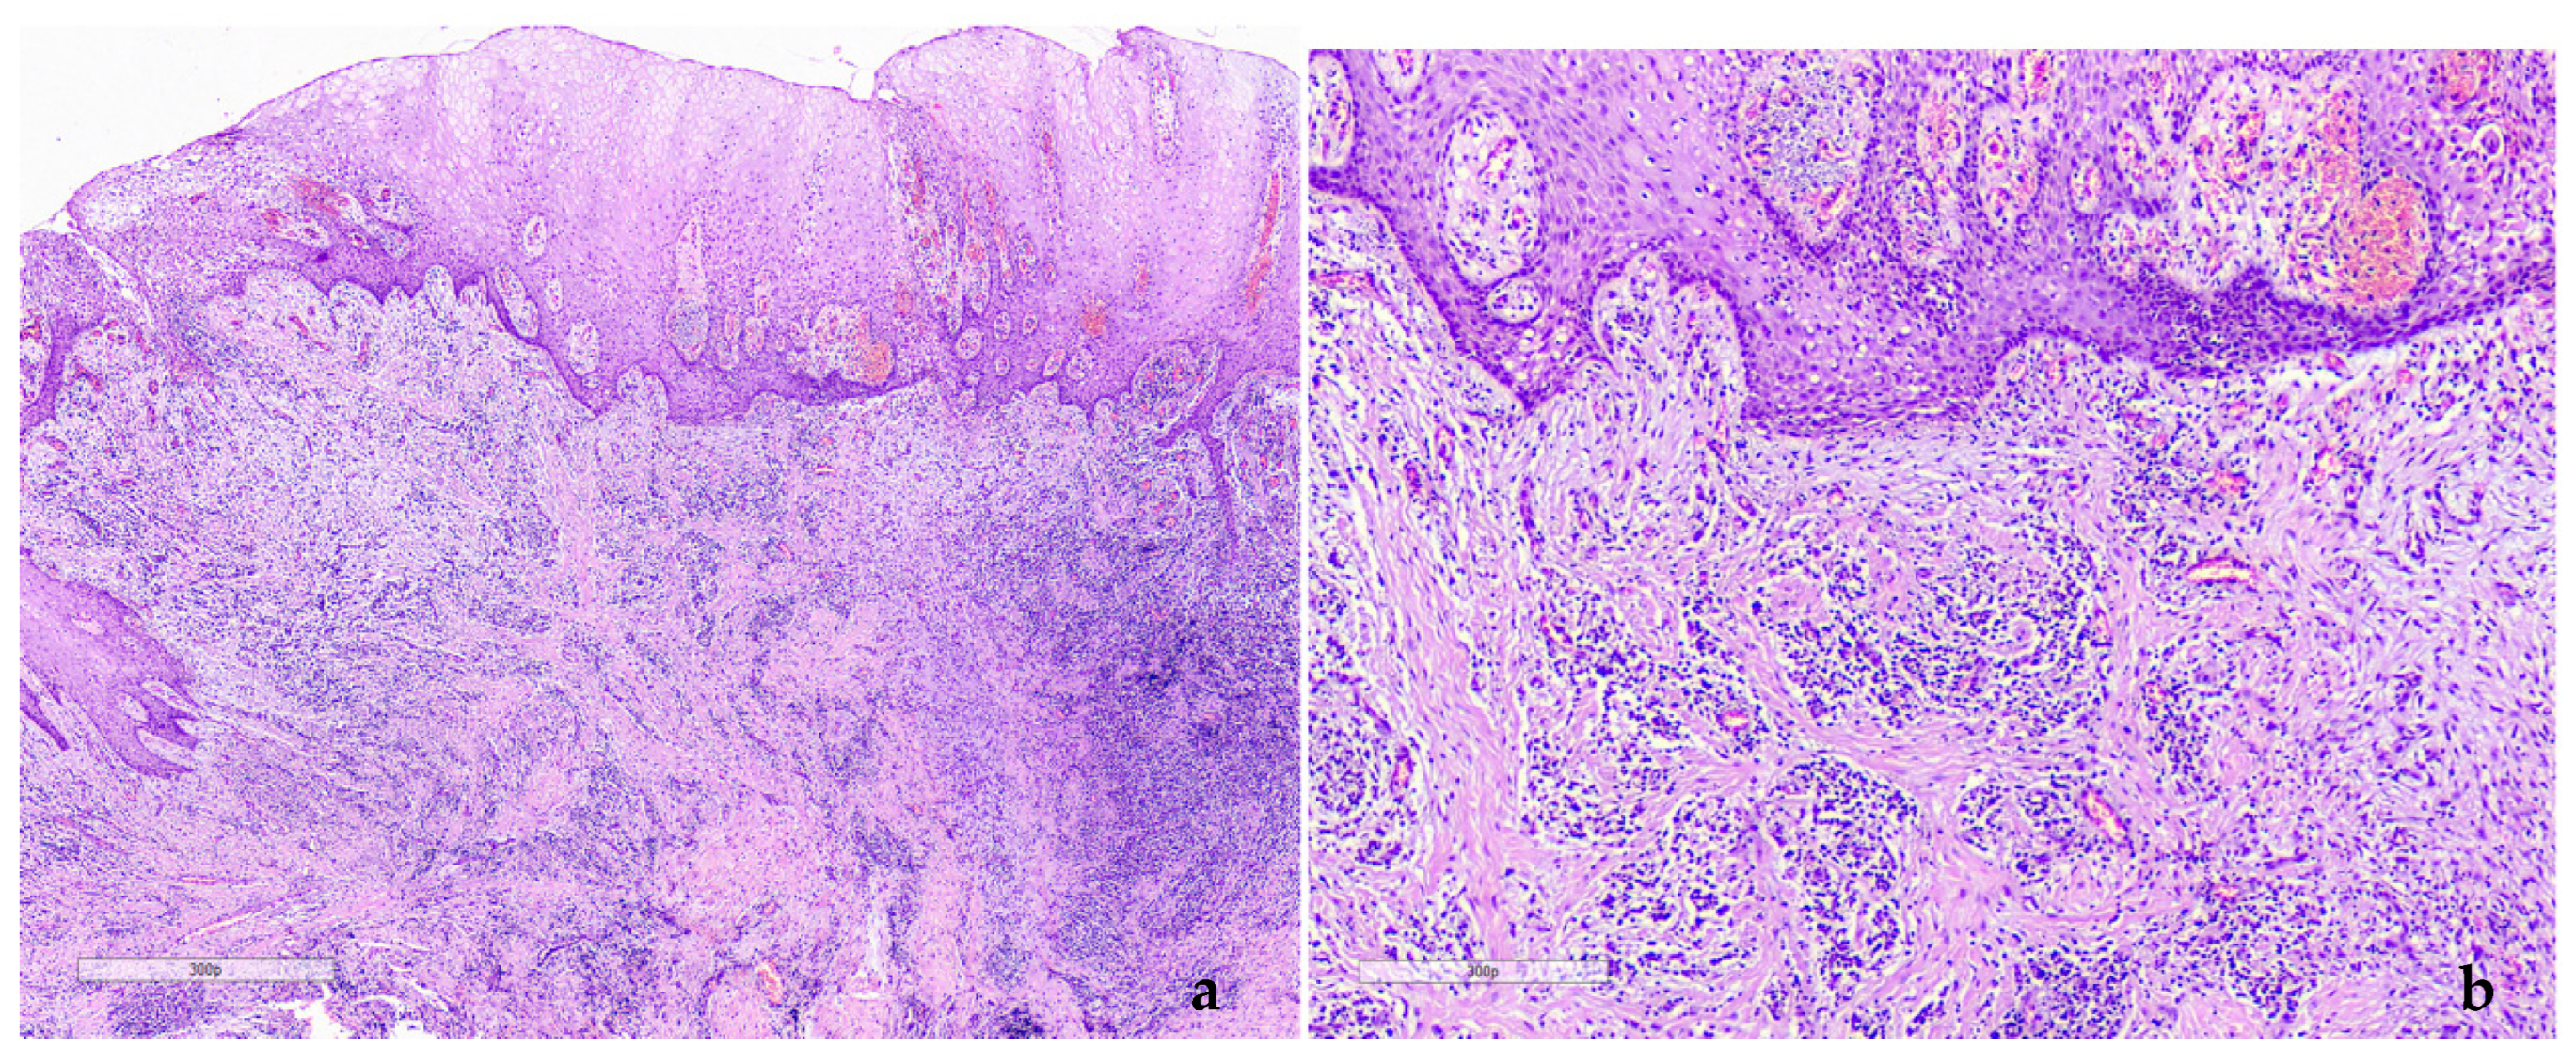

2.1. Case 1

2.2. Case 2